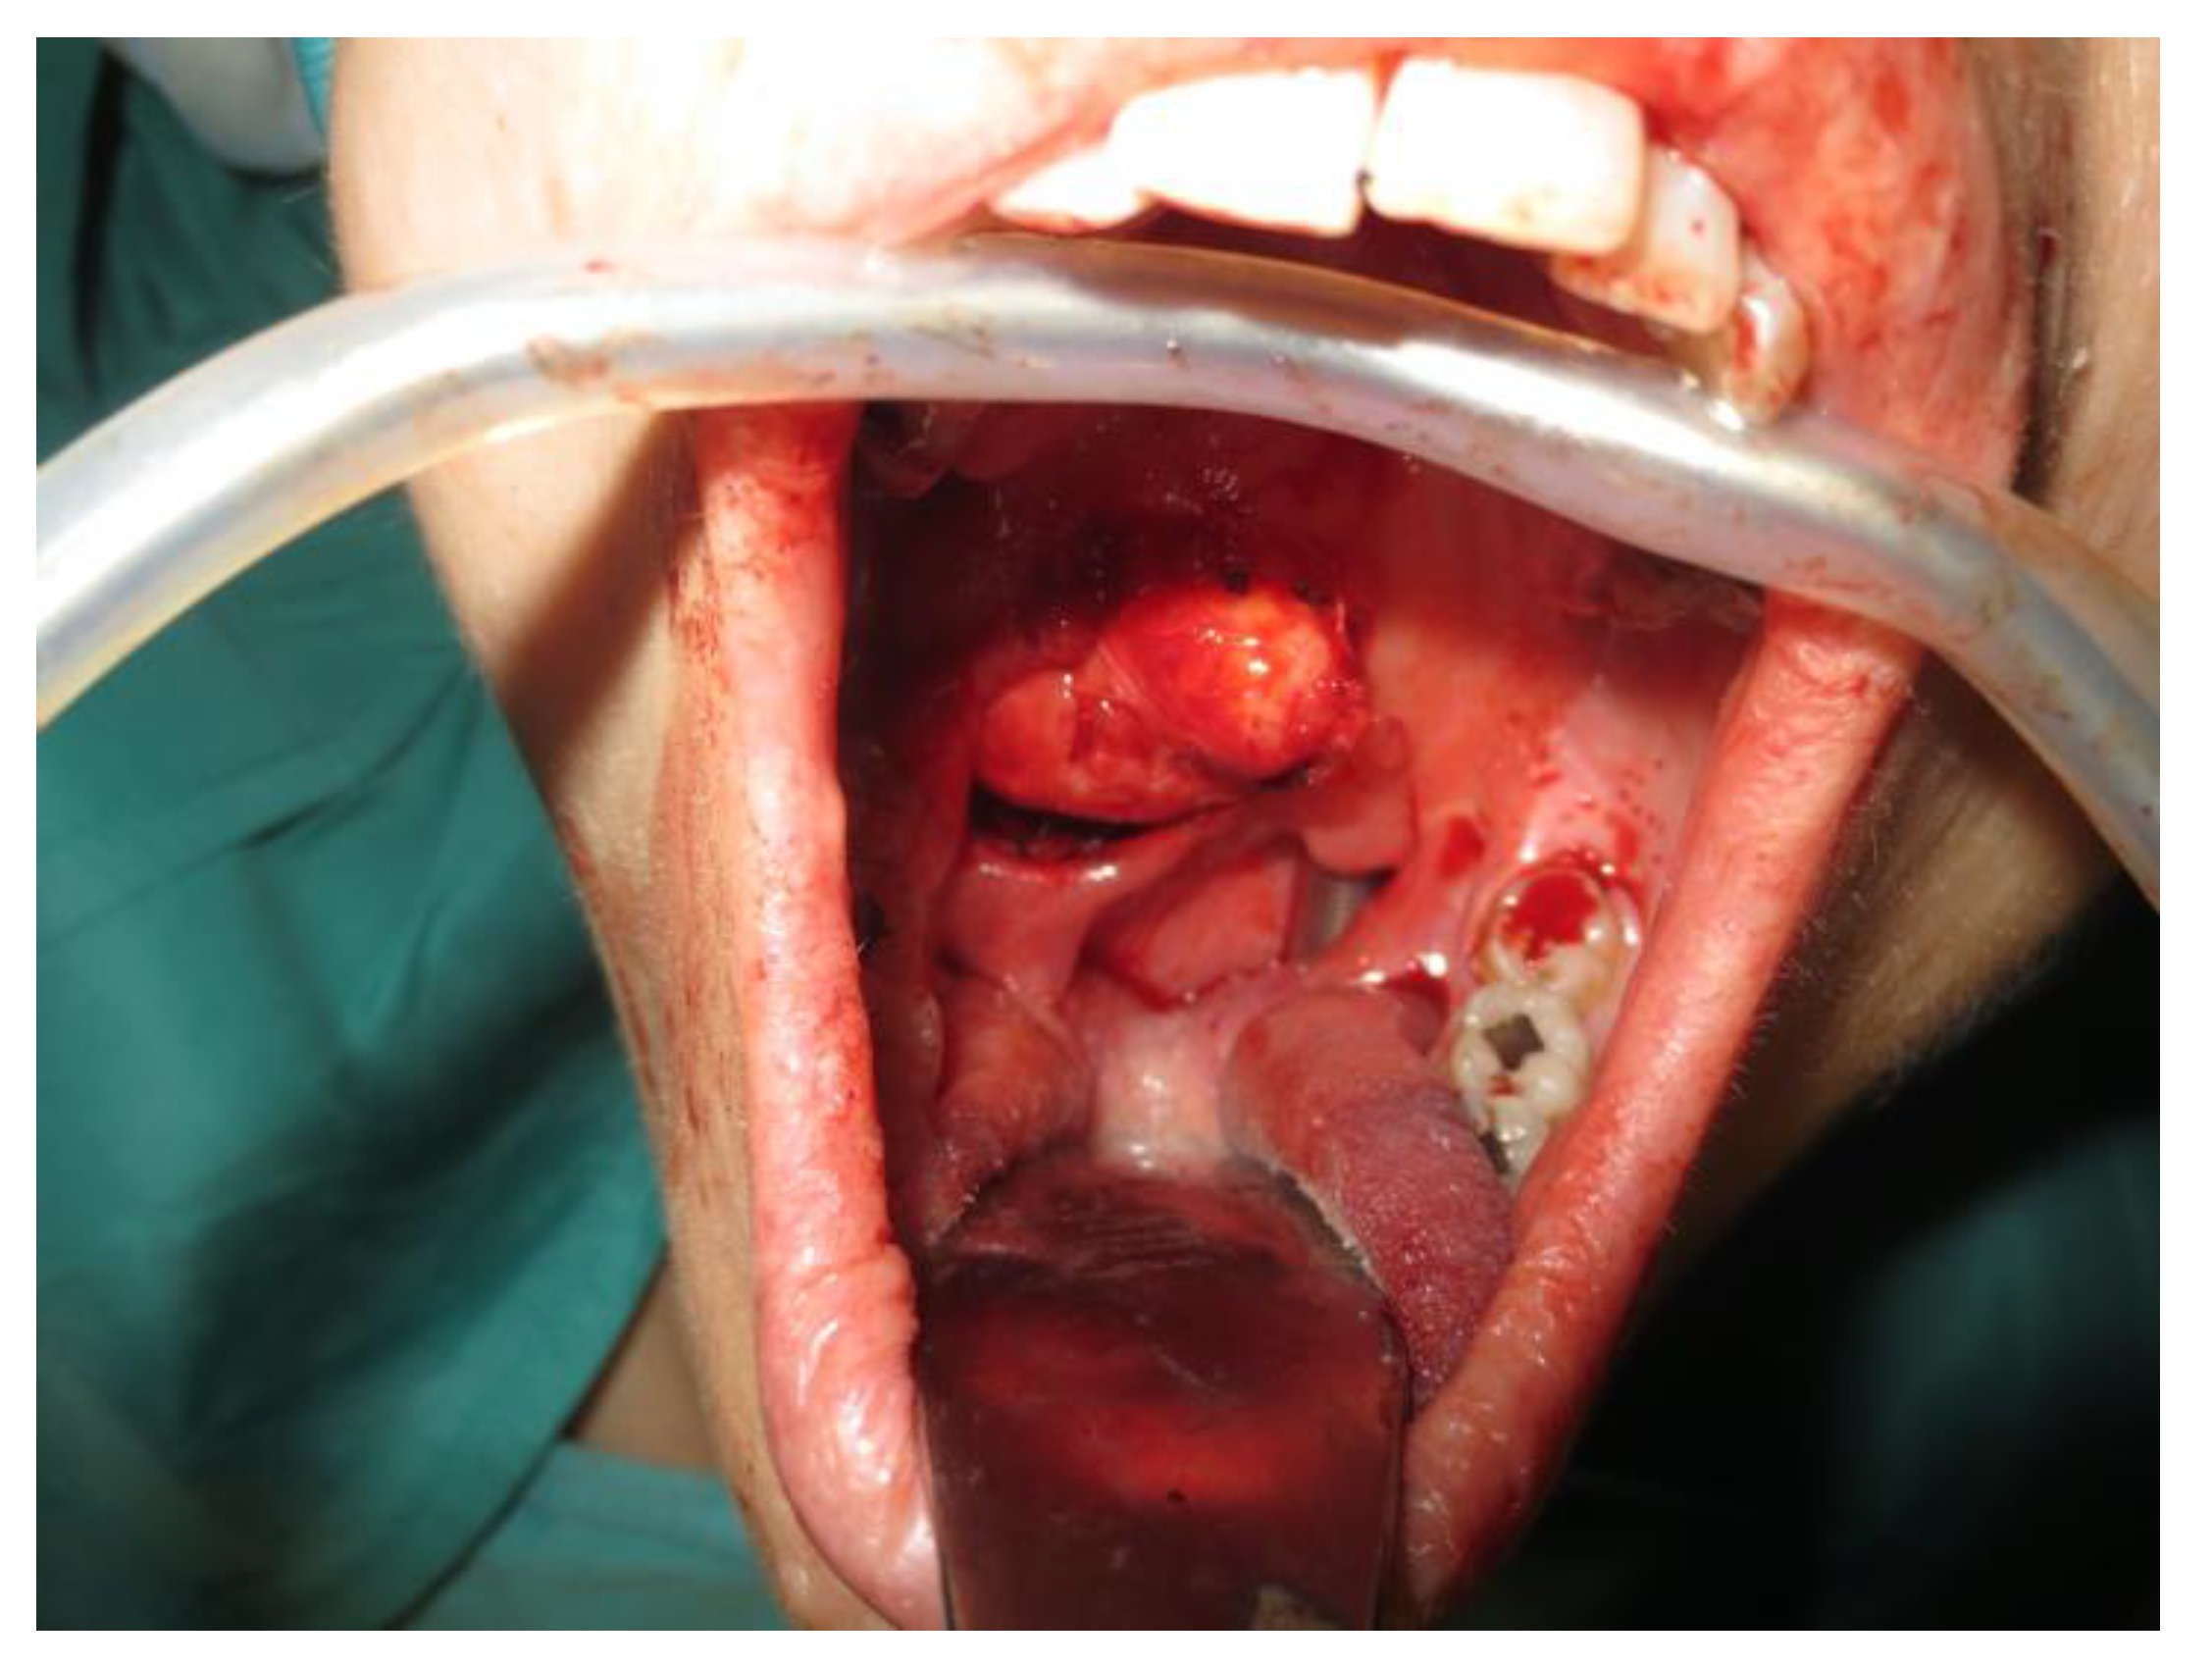

- Two schwannomas (Figure 5) originating from the cervical sympathetic chain and that arose in the superomedial aspect of the PPS, medially to the carotid sheath. The first patient underwent surgery in 2008, the second in 2019. No complications were observed during surgery and no tumour recurrence has been observed after 14 and 4 years, respectively. The only long-term complication observed was Horner syndrome (Figure 6), despite the continuity of the nerve not being interrupted. The hospitalisation time was three days for both patients.